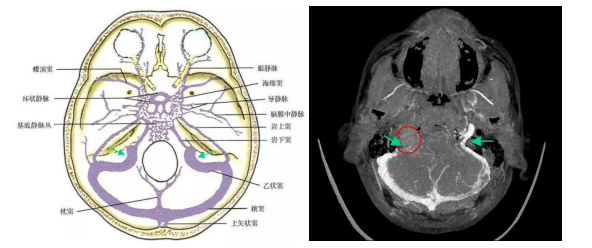

案例1:患者女,51岁,头晕1年余,行颅脑MRI检查示:“右侧桥小脑角区占位性病变”,收住神经外科拟行手术治疗,后经专家会诊,发现右侧桥小脑角区病变累及右侧颈静脉孔,为术前明确病变与颈内静脉的解剖关系,会诊专家提出行颈静脉成像(CTV)的诉求。

图1(左)为颅底静脉系统解剖示意图,图1(右)为脑静脉CTV后处理的最大密度(MIP)图像,红色圆圈表示肿瘤,绿色箭头表示双侧颈内静脉,图1(右)可清晰显示右侧颈内静脉于病变处闭塞。

图2(左)为脑静脉解剖示意图,图2(中、右)为脑静脉CTV后处理的容积再现(VR)图像,可清晰显示右侧颈内静脉闭塞。